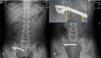

La radiografía evidenció una barra metálica con una cadena adyacente. Observándola detenidamente, se visualizaban zonas de discontinuidad, haciendo sospechar que pudiera tratarse de distintos CE con mucosa intestinal interpuesta (fig. 1A).

Durante su ingreso, se produjo un incremento del dolor en la FID. La radiografía a las 8 horas no evidenció modificación en la posición del CE (fig. 1B).